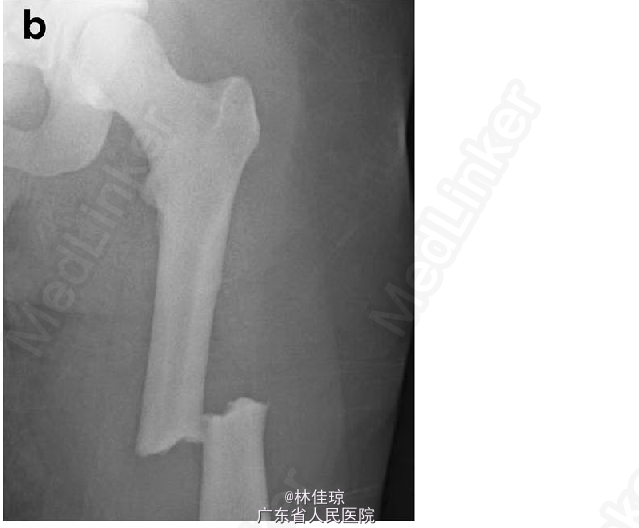

致密性成骨不全症合并股骨骨折 产科会诊后决定实施骨折切开复位内固定术,即:左侧股骨切开复位、髓内钉固定。术后 2 个月,患者分娩。分娩 2 周后双侧胫腓骨 X 线可见皮质增厚,另见胼胝体形成,与正常相比稍微减少,考虑到是不典型愈合,这与其破骨细胞功能紊乱相一致。手术 3 个月,患者左侧股骨疼痛明显减轻,但右侧股骨疼痛加重。X 线检查为右侧转子下不典型骨折。提议进行预防性手术,但患者本人拒绝。大约一周后,患者因跌倒后右侧下肢疼痛加剧就诊。X 线检查未见股骨进一步损伤。患者选择进行预防性固定术。

二次手术后 1 个月,患者状况良好且疼痛明显减轻。对侧手术亦无感染迹象。双侧股骨植入器位置放置合适。手术 1 年后,患者行走时几乎无疼痛,偶有双侧胫骨疼痛。X 线示双侧股骨愈合情况较好。DOI 10.1007/s00198-015-3191-1